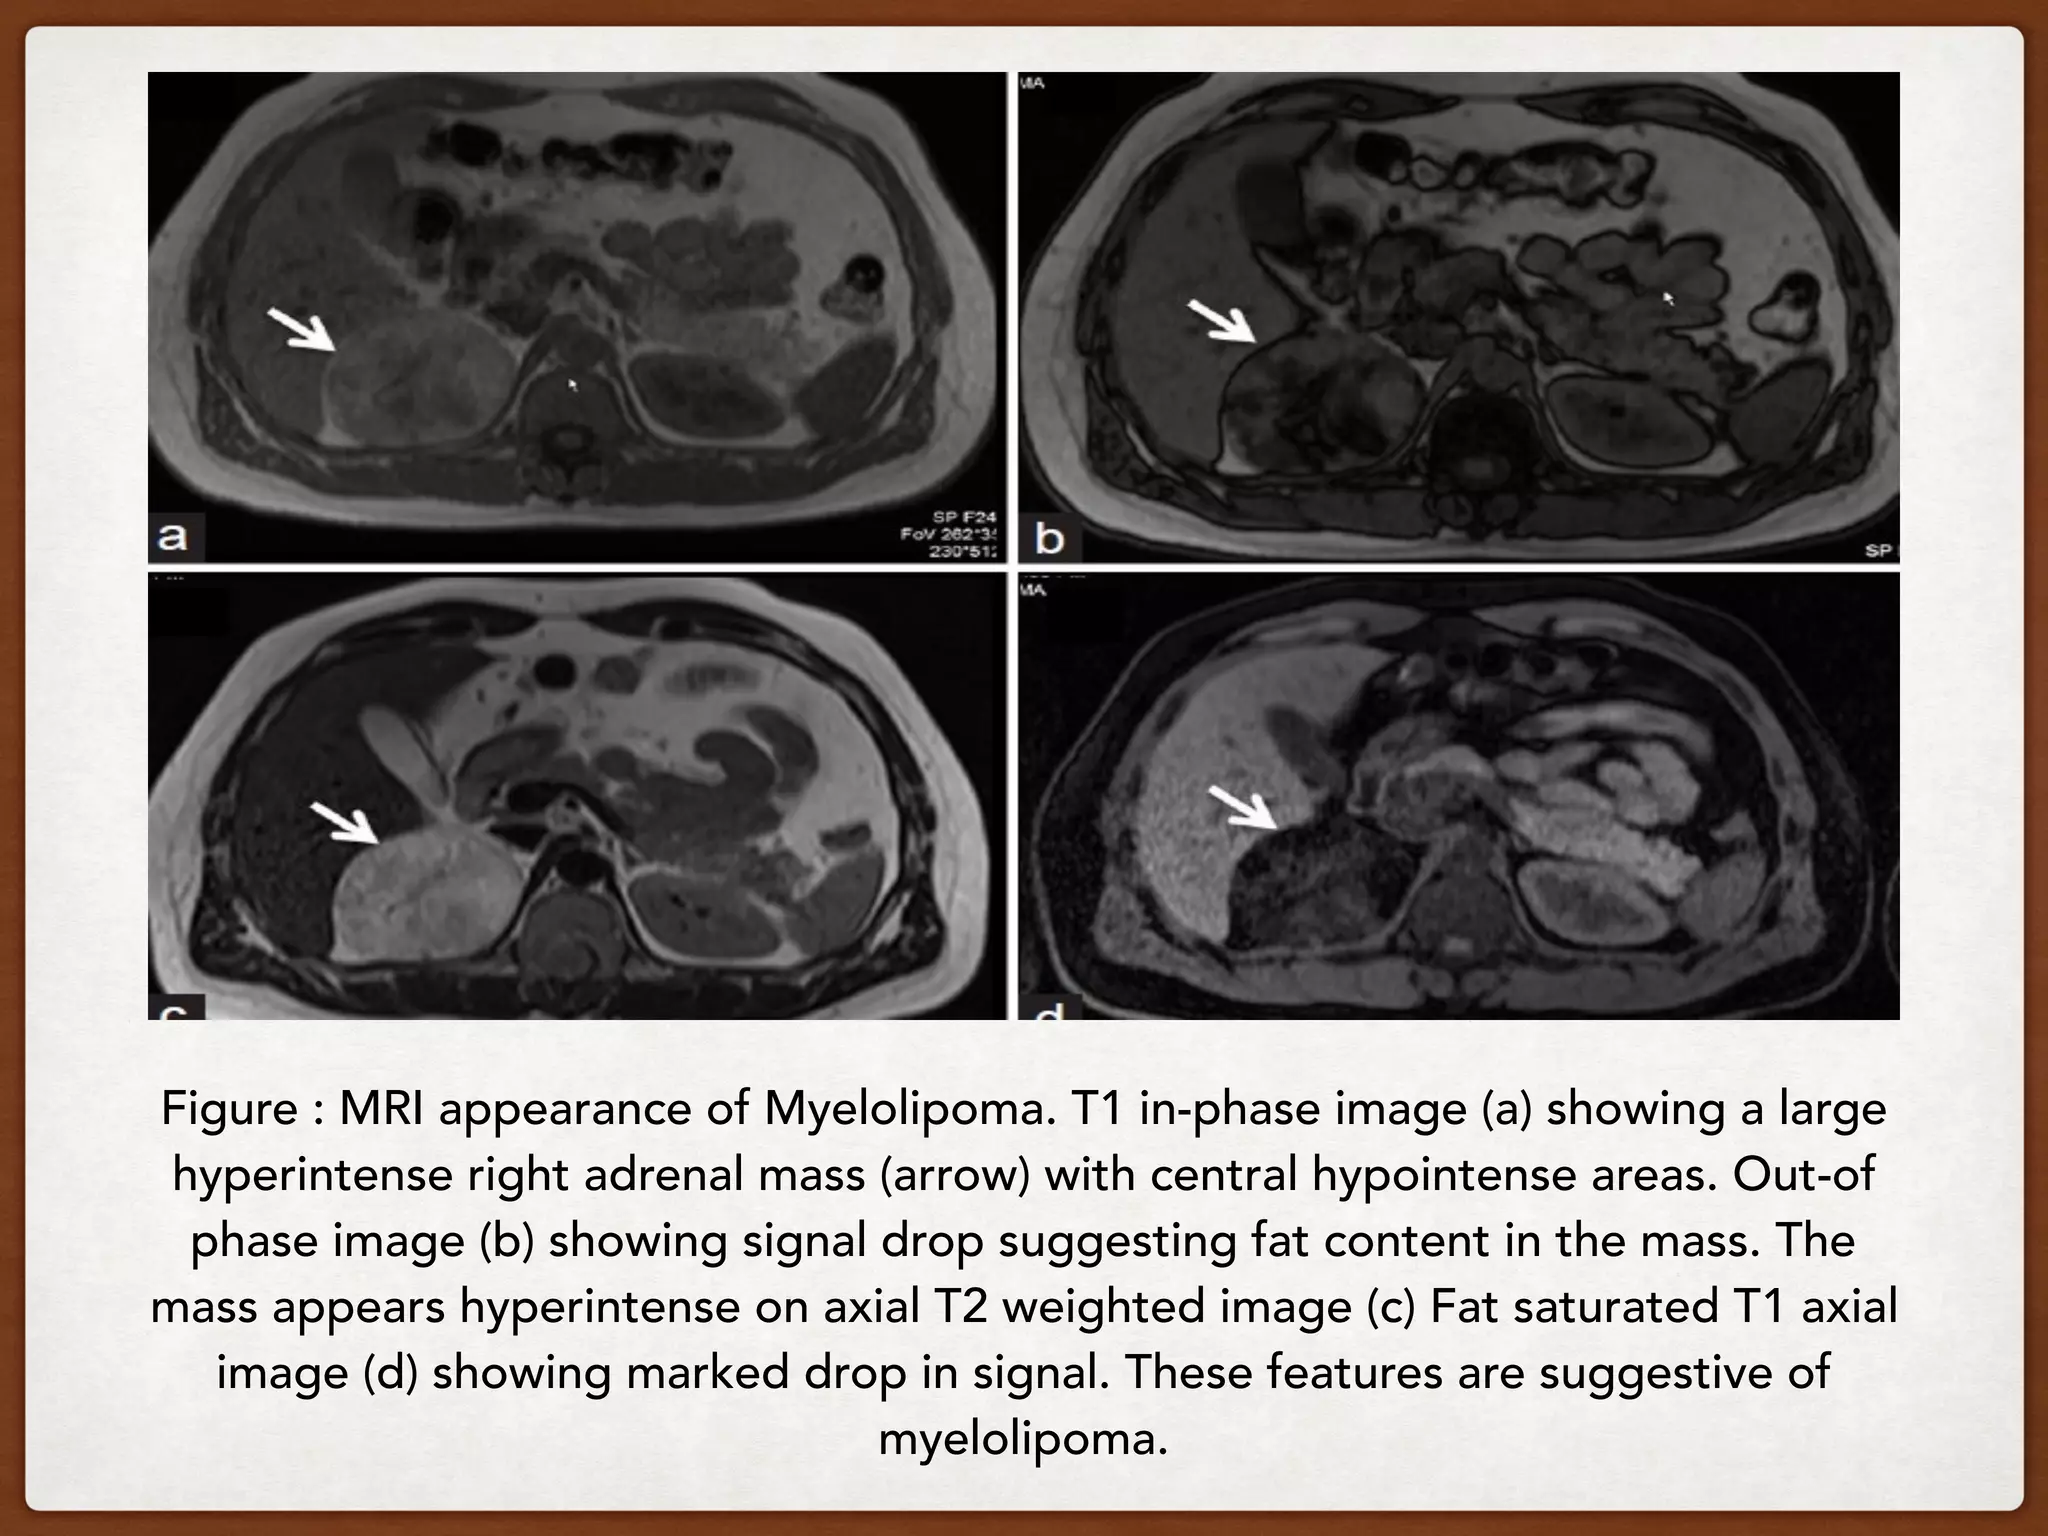

MRI

T1: typically hyperintense due to fat contents

T1 (FS): typically shows fat suppression

T2:  generally intermediate to hyperintense but can

sometimes vary depending on contents (especially

blood products)

T1 C+ (Gd):  shows striking enhancement( As it is

composed of variable mixture of mature fat and

hemapoetic elements that resemble bone marrow)

In and out of phase:  in masses with mixed

components, out of phase imaging may demonstrate

signal loss as the microscopic fat cells usually have

little intracellular water.

Figure : MRI appearance of Myelolipoma. T1 in-phase image (a) showing a large

hyperintense right adrenal mass (arrow) with central hypointense areas. Out-of

phase image (b) showing signal drop suggesting fat content in the mass. The

mass appears hyperintense on axial T2 weighted image (c) Fat saturated T1 axial

image (d) showing marked drop in signal. These features are suggestive of

myelolipoma.